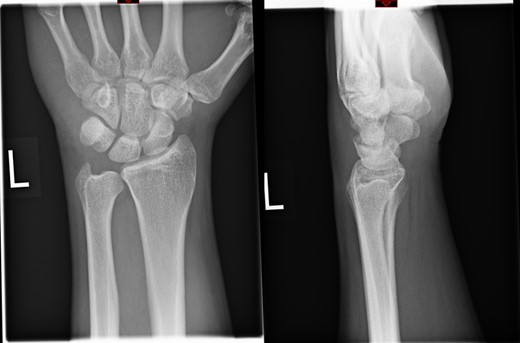

A 27-year-old male salesman, right hand dominant, was seen in the Emergency Department following a fall on to the outstretched hand while playing a game of rugby. He noticed immediate pain and swelling of the left wrist. Upon examination there was diffuse swelling on the dorso-medial aspect of the wrist. Tenderness was noted overlaying the ulna styloid process. He was non-tender to all scaphoid landmarks, metacarpals and phalanges. There was restricted range of motion of the wrist but full range of movements of the digits. There was no distal neurovascular deficit. The radiological examination of the left wrist was interpreted by the emergency doctors as no bony injury. A diagnosis of wrist sprain was made and was therefore treated with analgesia, ice application and a wrist splint as per local policy.

The X-rays of the patient was later reviewed by the duty radiologist and reported as a suspected dislocation of the pisiform bone, Fig. 1. Therefore the patient was recalled to the trauma clinic after three days. He was reassessed and a further three dimensional scan of the wrist was arranged. The CT scan demonstrated distal dislocation of the pisiform which appeared to lie in a ‘locked’ position beyond the distal triquetrum, Fig. 2.

Radiograph at 3 months showing pisiform bone anatomically reduced and maintained.